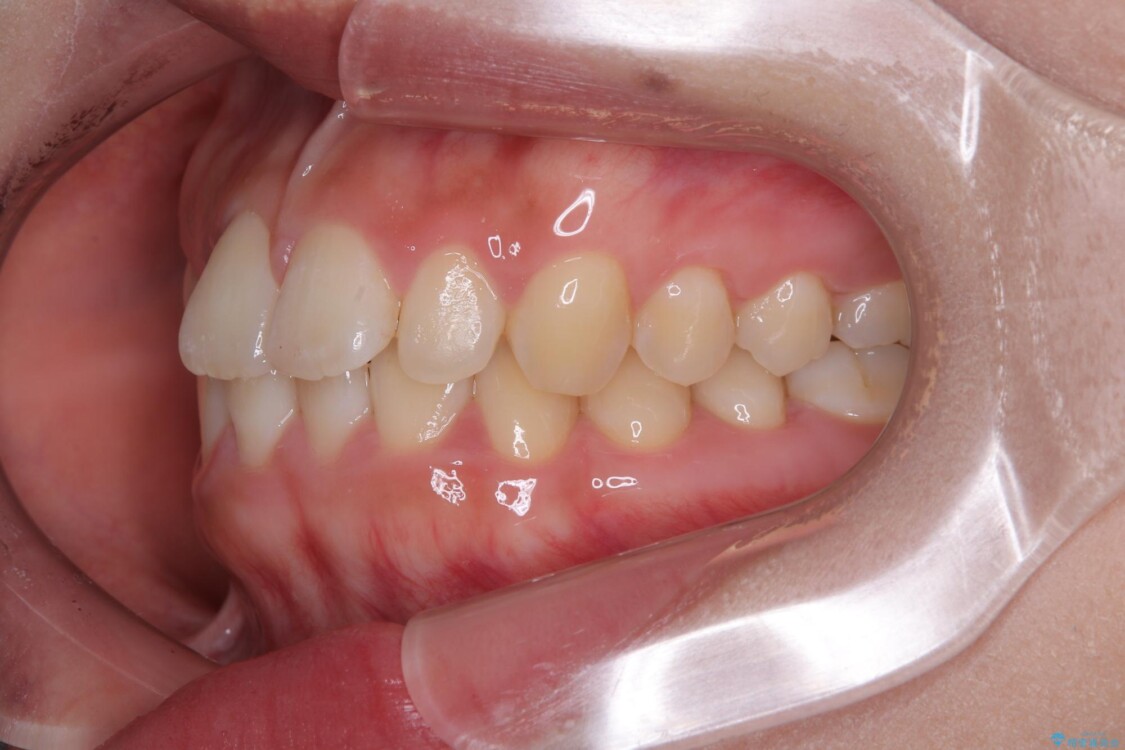

前歯のデコボコが気になるでのことで来院された患者様です。

歯列アーチが狭くスペース不足により前歯がデコボコしている状態でした。見た目を改善しつつ、前歯を前方に突出させず、自然な笑顔を目指したいというご希望でした。

治療前

• 目立ちにくい表側装置で1年完了!狭いアーチを側方拡大し前歯のデコボコを整えた症例 治療前画像